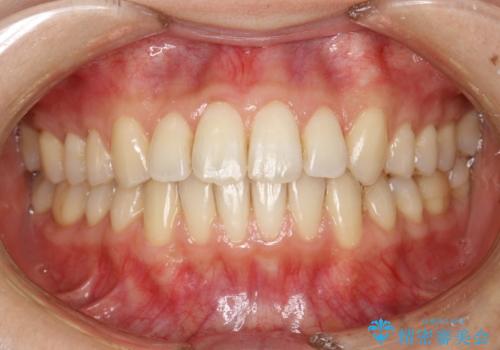

前歯のガタガタをインビザラインで目立たず矯正

- 目立たずに前歯を矯正したいとのことで来院されました。

歯と歯の間にわずかに隙間を作りスペースを確保し、インビザラインにて矯正を行うこととなりました。

前歯の微調整に少し時間がかかりましたが、整った歯並びにすることができました。